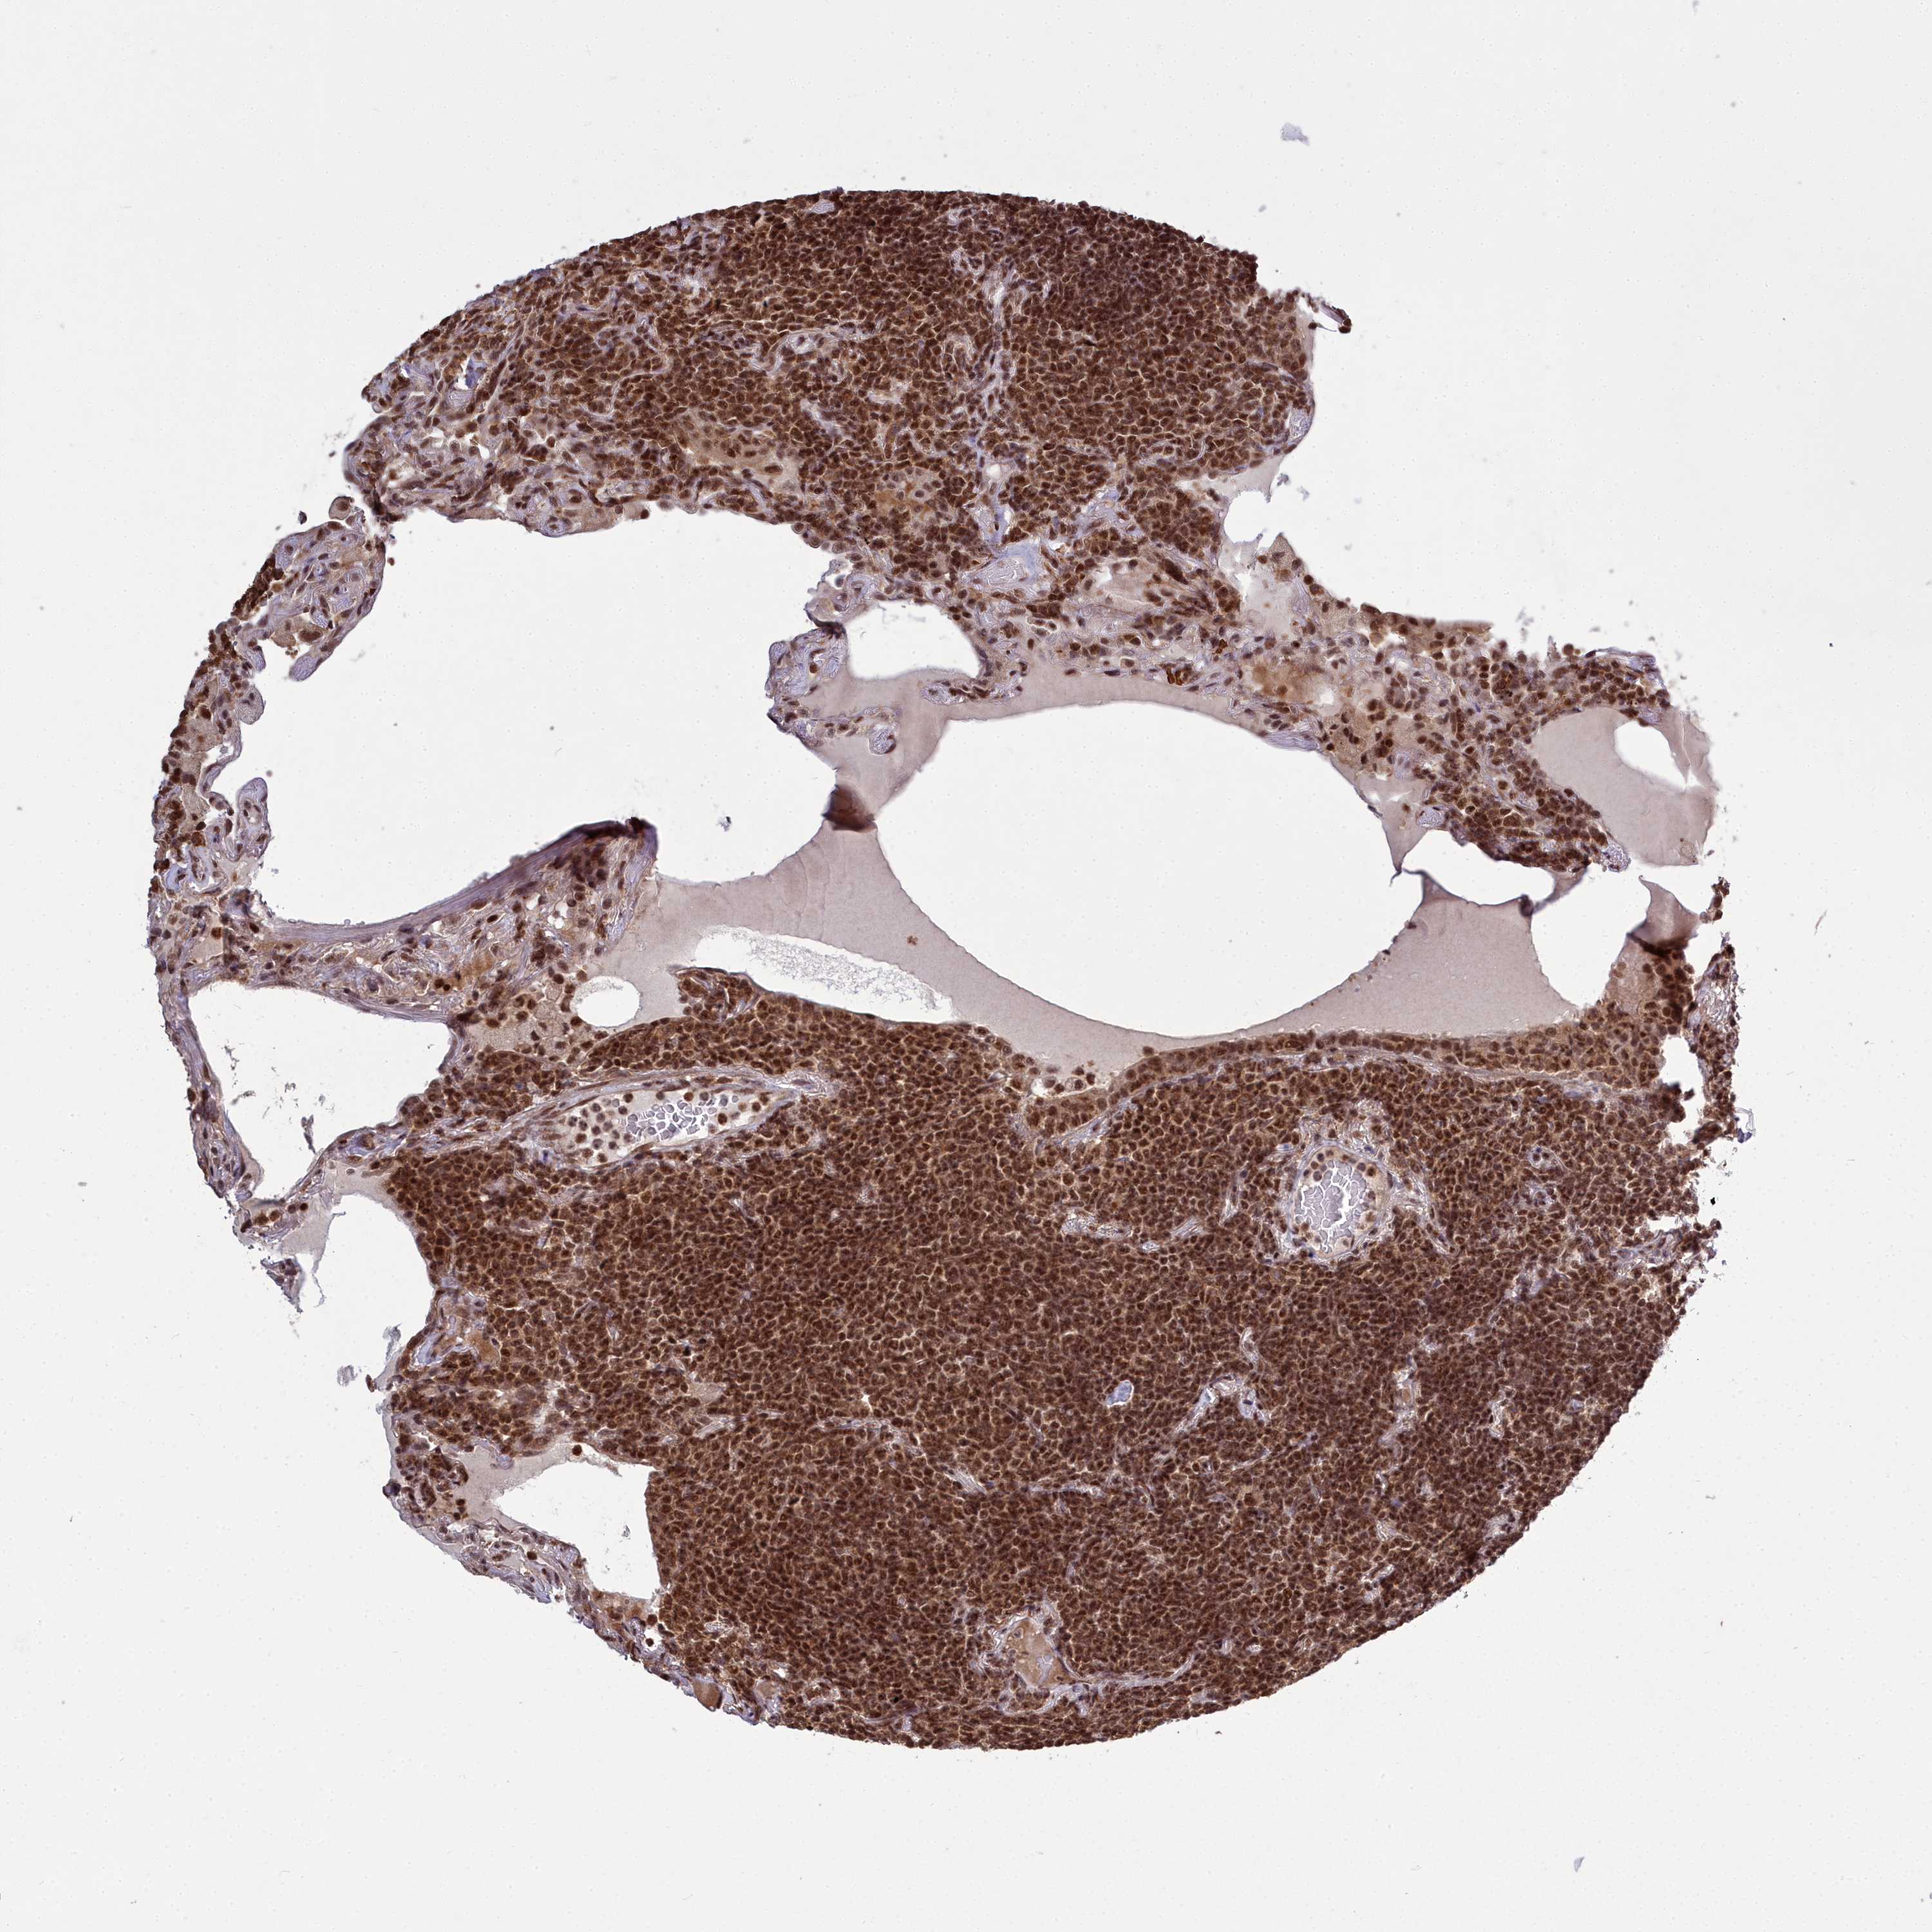

CANCER LYMPHOMA Show tissue menu

LYMPHOMA - Protein expressioni

A mouse-over function shows sample information and annotation data. Click on an image to view it in a full screen mode. Samples can be filtered based on level of antibody staining by selecting one or several of the following categories: high, medium, low and not detected. The assay and annotation is described here.

Each image is clickable and will lead to virtual microscopy that enables deeper exploration of all samples and also displays staining intensity scores, fraction scores and subcellular localization as well as patient and tissue information for each sample.

Antibody HPA044811

Staining

High

Intensity

Strong

Quantity

>75%

Location

Nuclear

Hodgkin's disease, NOS

Malignant lymphoma, non-Hodgkin's type, High grade

Malignant lymphoma, non-Hodgkin's type, Low grade